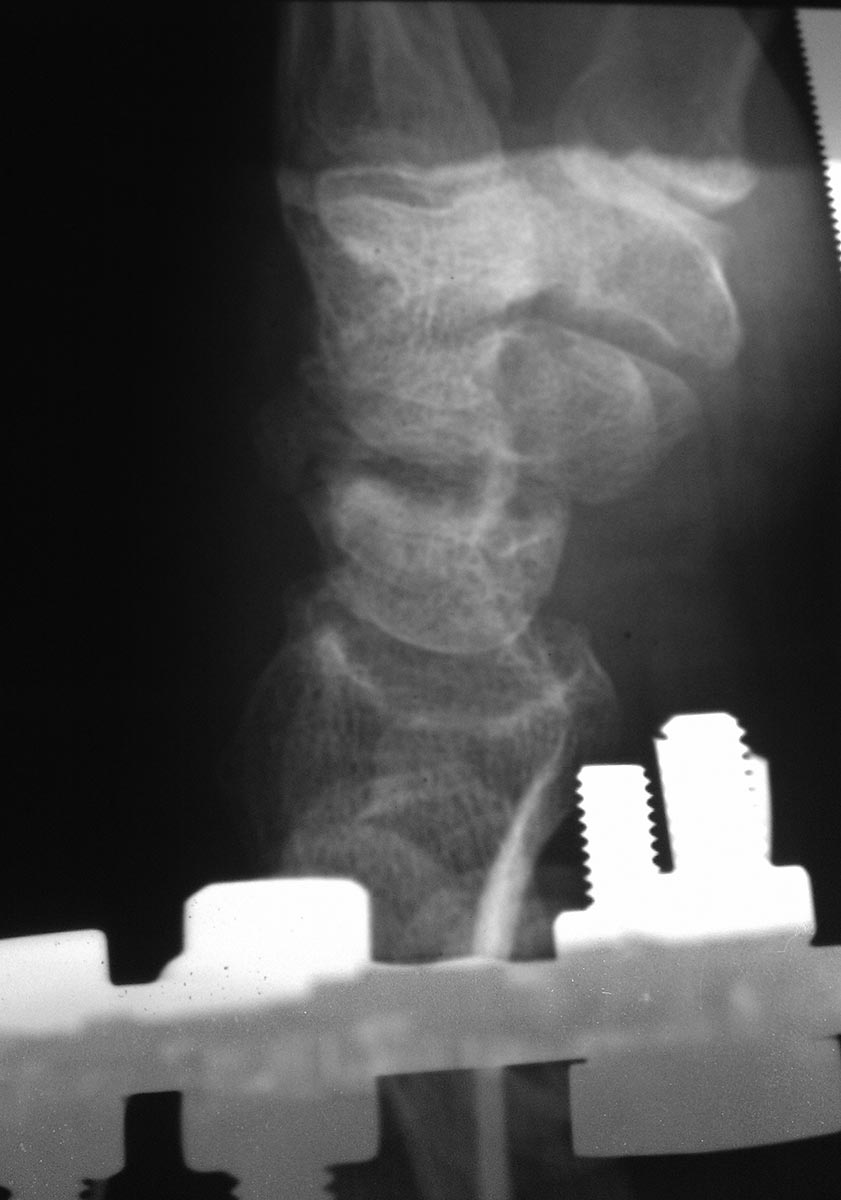

Снимок от 18.03.16 после закрытой репозиции на аппарате Илизарова.

Сомнения есть, что написано доктором. Травматолог предоставил бы диагностические Rg-граммы в двух проекциях после репозиции, озадачился бы компьютерной топографией запястья. А, у травматологов в ординаторской есть негатоскоп и фото рентгенограмм лучше выполнять с него, чтобы не изучать припаркованные машины за окном. Судя по снимку: что-то с ладьевидной костью.

Свежего перелома не вижу. Есть несросшийся перелом ладьевидной кости. Также артроз л/зап. сустава уже есть, видимо травма старинная.

перелом явно старый, более 1 года. Сформировался ложный сустав, есть признаки артроза. Учитывая молодой возраст, возможно стоит рассмотреть остеосинтез винтами Герберта с костной аутопластикой. Надо зачистить шип на ладье, возможно удалить верхушку шиловидного отростка лучевой кости. Еще- в плане личного восприятия- снимки и репозиция все-таки делаются В АППАРАТЕ, а не НА.

Ложный сустав ладьевидной кости не вызывает сомнений, причём до 4.02.2016 - без клинической манифестации. 4.02.2016-травма и подвывих на уровне ложного сустава.